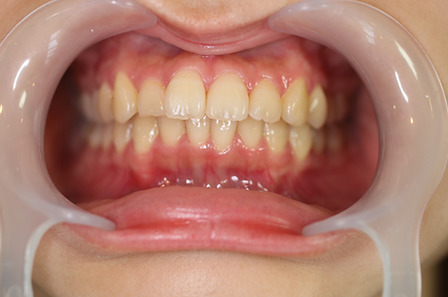

2ホワイトニング【治療例2】

治療前

治療後